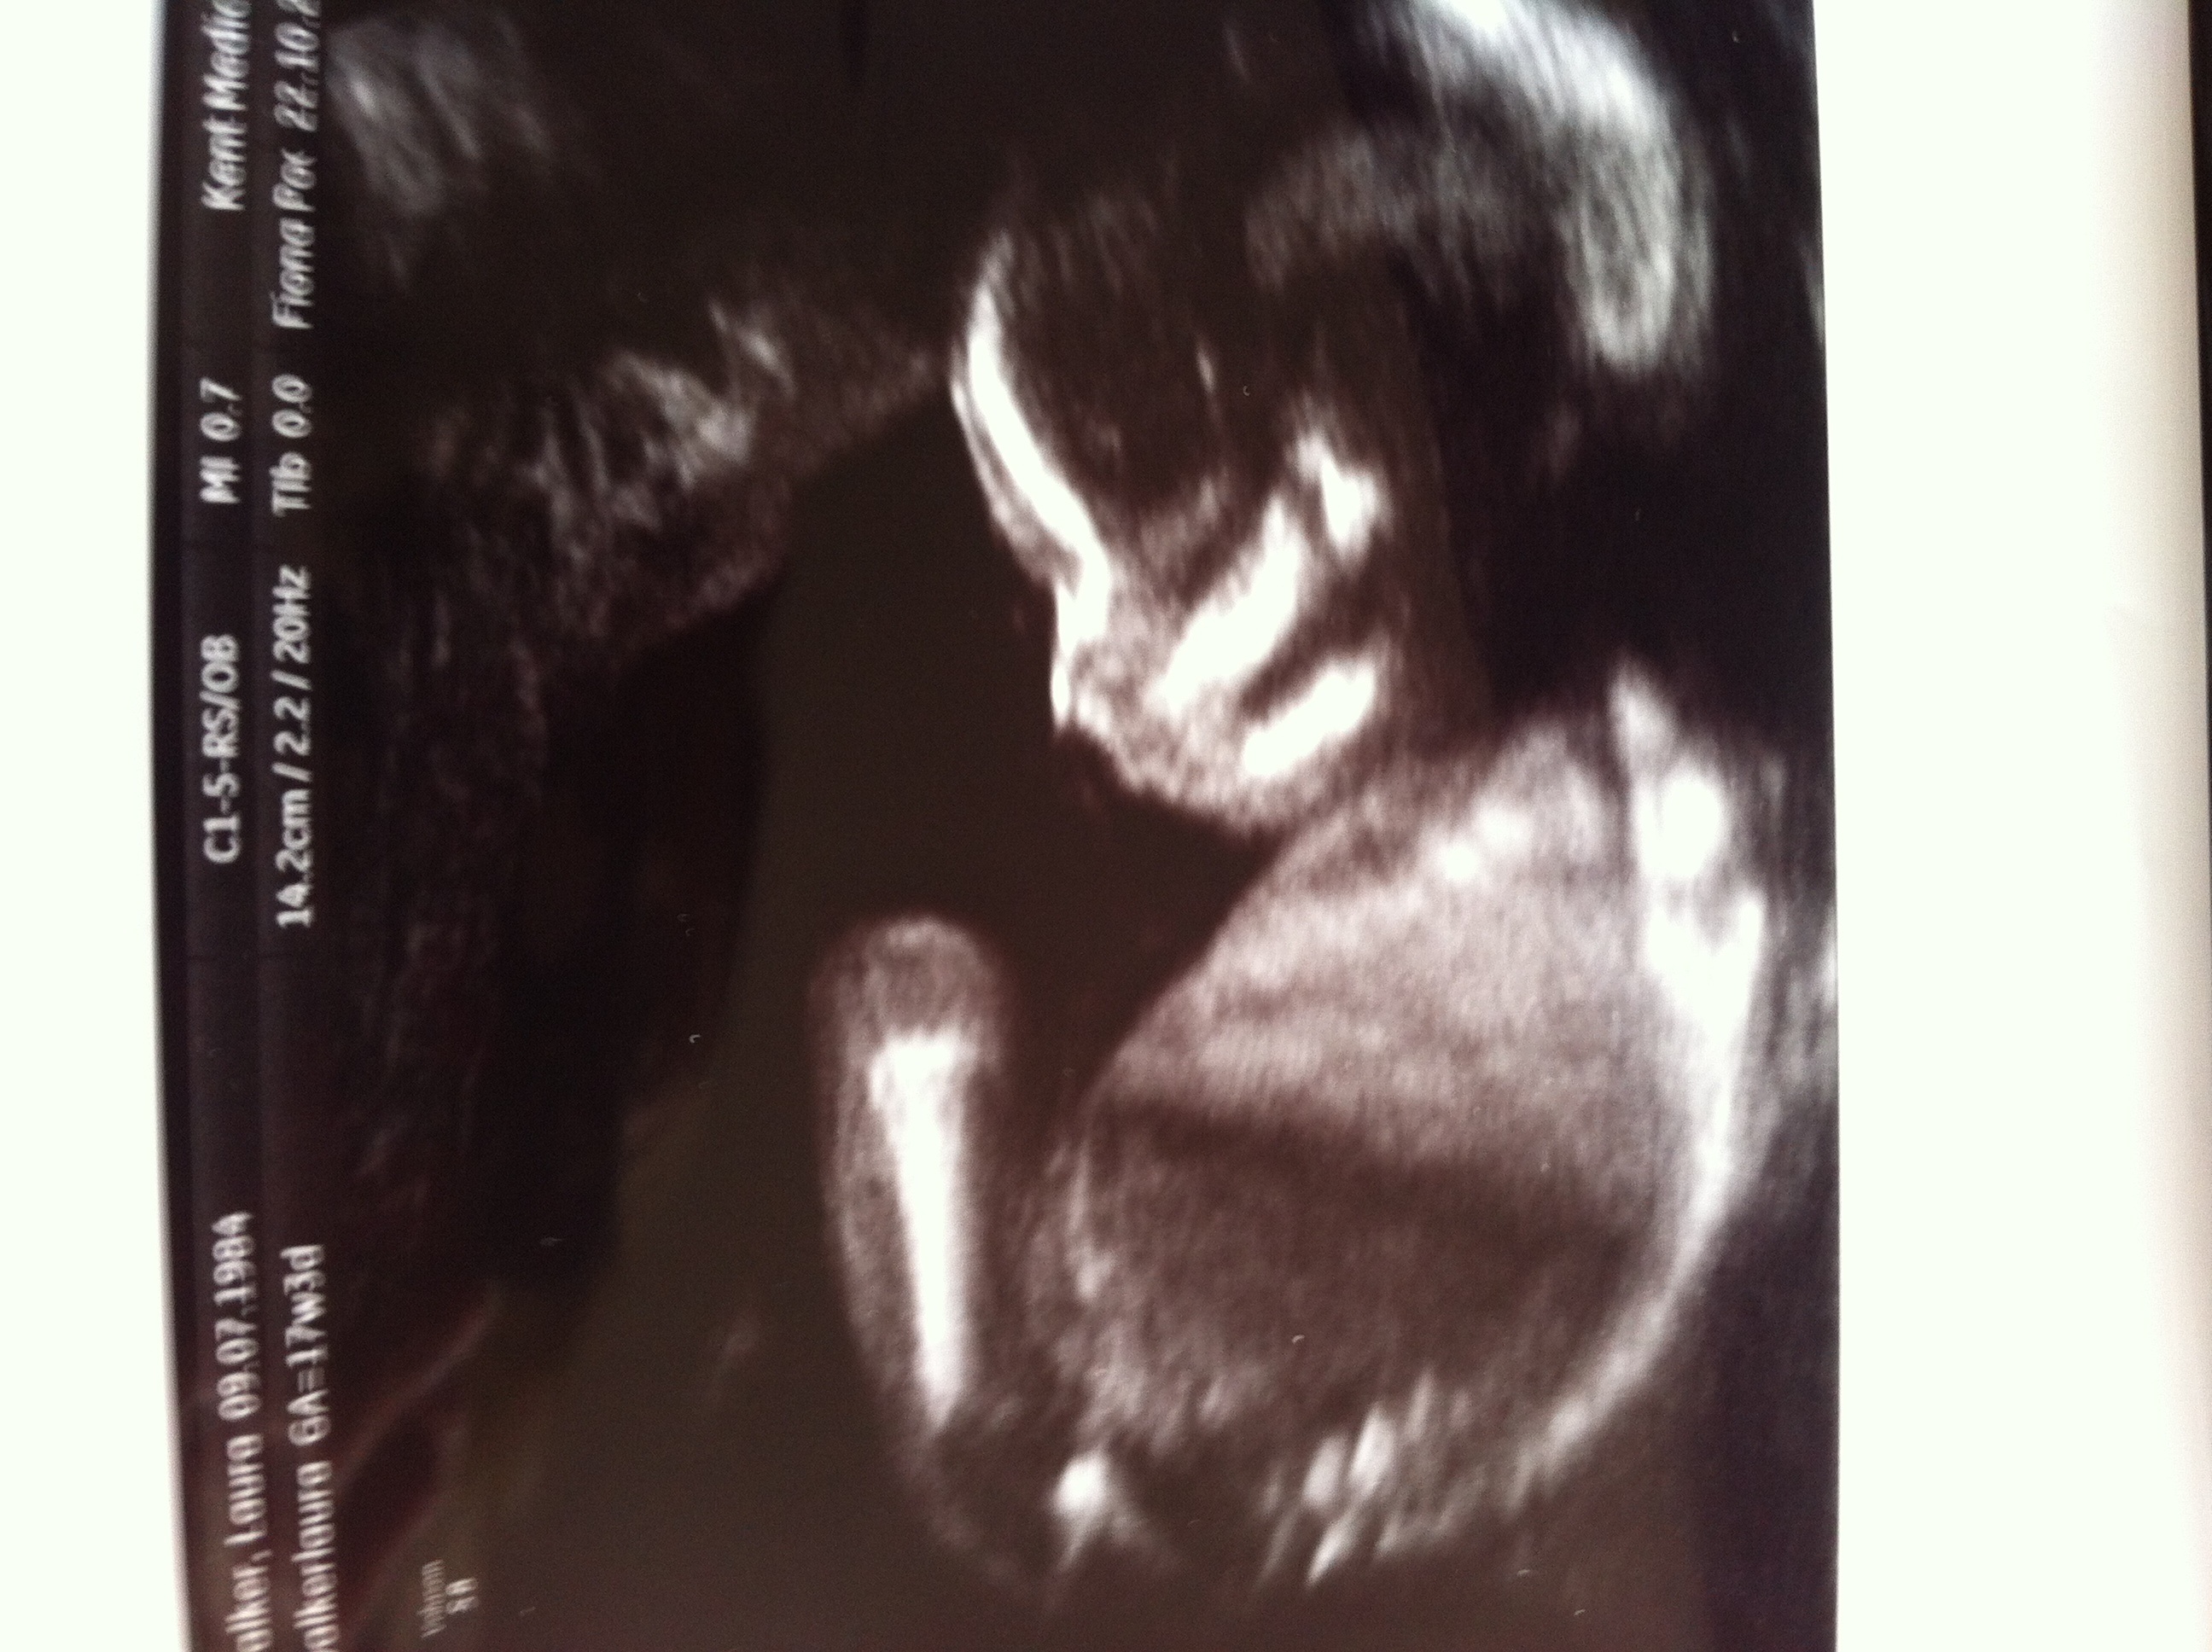

Do u think tech was correct she couldn't say 100%

That's a girl :)

Girl

Thank u ladies hopefully will get it confirmed at 20 weeks x

Girl!!!

I think girl.

Oh yes that's a Girl, Congratulations!